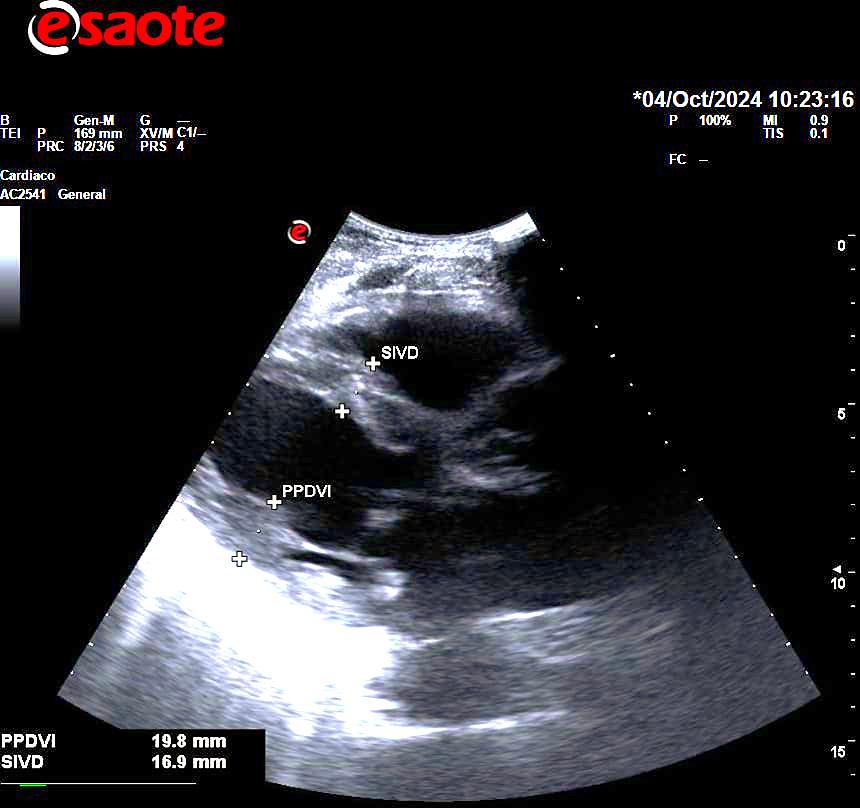

En la ecocardioscopia, se aprecia leve dilatación de aurícula izquierda, septo interventricular de 18 mm sin obstrucción del tracto de salida, FEVI estimada mayor del 55% sin segmentarismos ni discinesias, raíz aórtica normal, válvula aórtica trivalva, buena apertura de válvula mitral, no derrame pericárdico.

Miocardiopatía Hipertrófica.